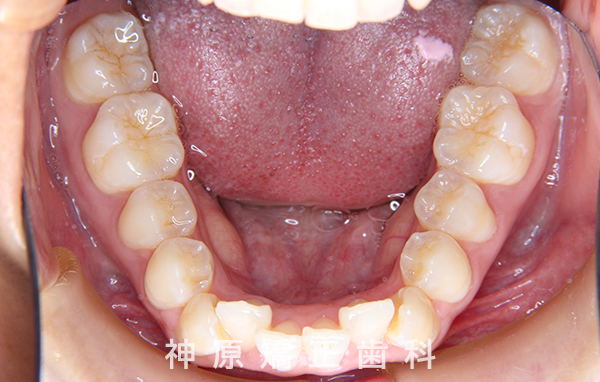

初診時